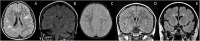

Relapsing demyelinating syndromes (RDS) in children encompass a diverse spectrum of entities including multiple sclerosis (MS) acute disseminated encephalomyelitis (ADEM), aquaporin-4 antibody associated neuromyelitis optica spectrum disorder (AQP4-NMOSD) and myelin oligodendrocyte glycoprotein antibody disease (MOG-AD). In addition to these, there are "antibody-negative" demyelinating syndromes which are yet to be fully characterized and defined. The paucity of specific biomarkers and overlap in clinical presentations makes the distinction between these disease entities difficult at initial presentation and, as such, there is a heavy reliance on magnetic resonance imaging (MRI) findings to satisfy the criteria for treatment initiation and optimization. Misdiagnosis is not uncommon and is usually related to the inaccurate application of criteria or failure to identify potential clinical and radiological mimics. It is also notable that there are instances where AQP4 and MOG antibody testing may be falsely negative during initial clinical episodes, further complicating the issue. This article illustrates the typical clinico-radiological phenotypes associated with the known pediatric RDS at presentation and describes the neuroimaging mimics of these using a pattern-based approach in the brain, optic nerves, and spinal cord. Practical guidance on key distinguishing features in the form of clinical and radiological red flags are incorporated. A subsection on clinical mimics with characteristic imaging patterns that assist in establishing alternative diagnoses is also included.